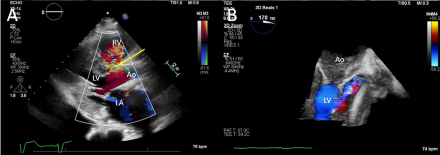

Case Description: An 80-year-old woman with history of hypertension, HFpEF, and TAVR 8 months prior for severe aortic stenosis (AS) at an outside hospital presented with worsening dyspnea and peripheral edema over the past month. Blood pressure was 148/53mmHg, heartrate 83bpm, oxygen saturation 98% and auscultation revealed a harsh holosystolic murmur 4/6 loudest at left sternal border and bibasilar rales. Chest X-ray showed pulmonary edema and bilateral pleural effusions. NT-proBNP was 17,000pg/ml and troponin-I was negative. Echocardiogram showed EF55-60%, a membranous VSD, severe pulmonary hypertension, and moderate paravalvular leak (PVL). Coronary angiogram showed non-obstructive disease. Right heart catheterization confirmed significant left to right shunting.

Treatment/Outcomes: Cardiothoracic surgery was consulted for multidisciplinary evaluation, and joint recommendation was for surgical aortic valve replacement and VSD closure which was successfully performed. One month follow-up echocardiogram showed normal aortic valve gradient without PVL and normal right ventricular pressure.

Discussion/Conclusion: Numerous potential risks such as severe and uneven calcification of the native valve, an elliptic aortic annulus, excessive valve sizing, or elevated valve placement can lead to VSD. A recurrent element in many of these instances involves direct trauma to the septum caused by the implanted valve, exacerbated by subsequent annulus dilation. The presence of PVL is common post-TAVR and is an established independent prognostic factor, while VSD post-TAVR is uncommon, but may be associated with low implantation position relative to the aortic annulus or post-implantation balloon dilatation. Rarely, worsening VSD may require operative management. In this case, the improvement of heart failure symptoms and echocardiogram parameters after transthoracic surgery confirmed successful repair.